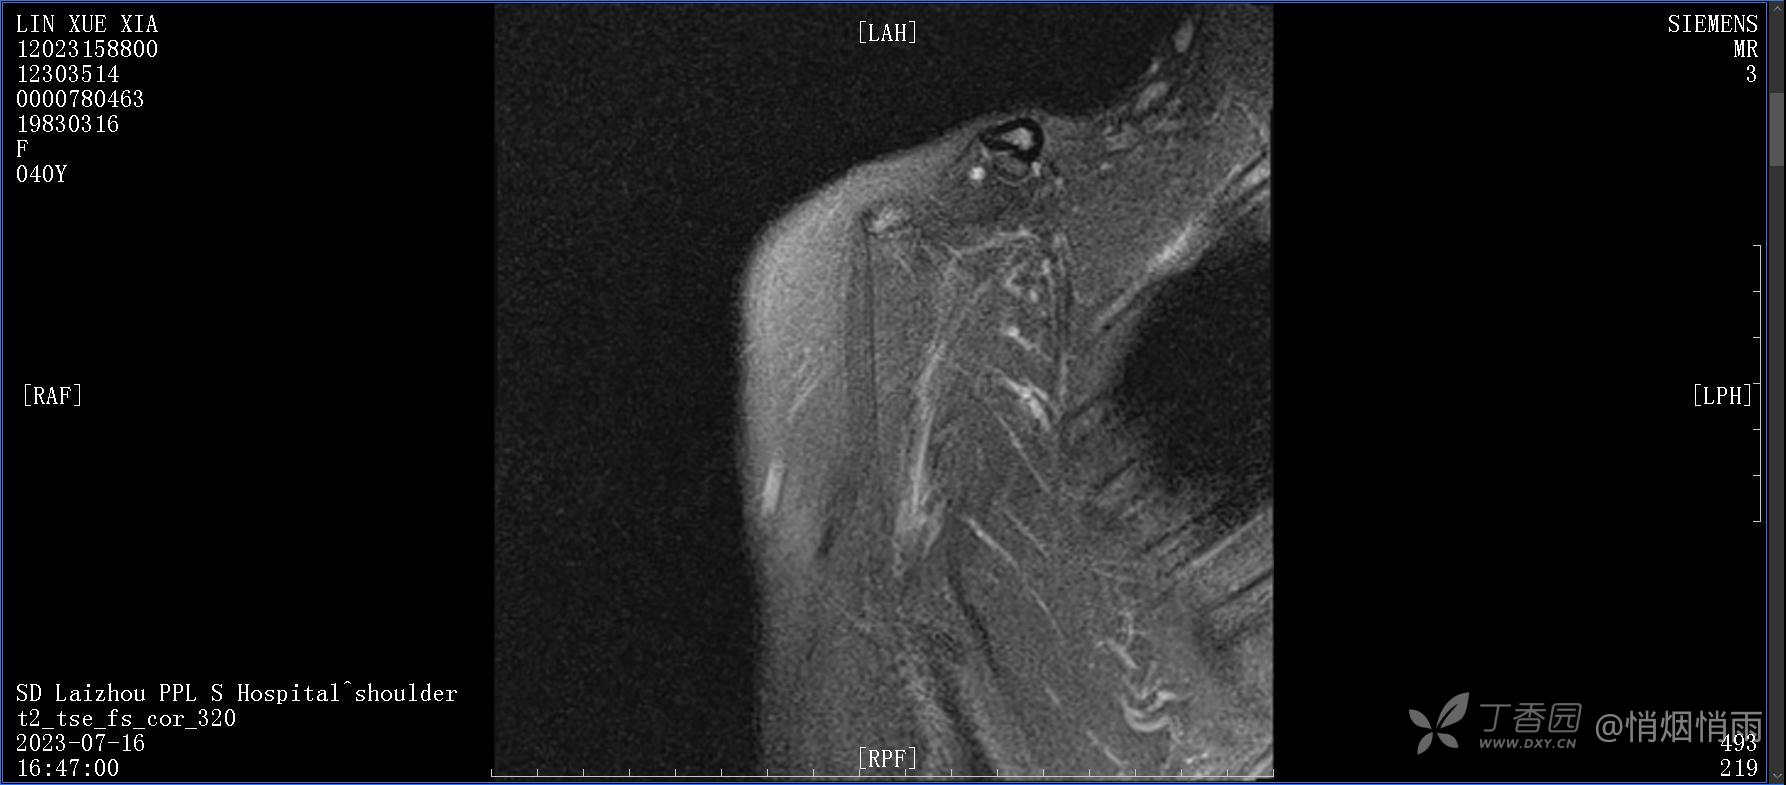

查体:右肩关节局部轻度肿胀,肩胛区压痛明显,痛处不固定,肩关节痛性活动受限,jobe test(+),lift -off test(+),中指、环指感觉较余指减退,余肢端感觉及血运情况可。

目前的诊断,暂时依据辅助检查诊为肩袖损伤,但是患者疼痛的性质和特点,却不是单纯的肩袖损伤所致。考虑过胸廓出口综合征,但是该疾病会出现肩胛区的疼痛吗?(由于考虑到费用的问题,没再进行下一步的检查)带状疱疹会有如此的症状吗?